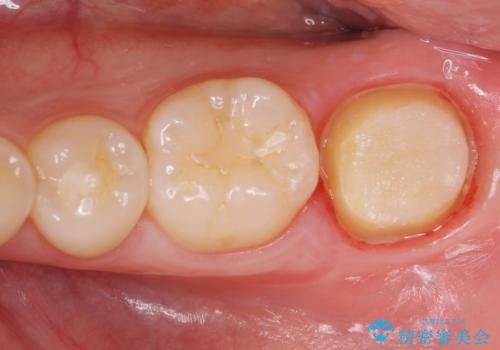

他院での治療に不信感 虫歯除去後のジルコニアクラウン

- 歯が痛くなり、他院で治療してもらったところ不信感があり、当院に受診に来られました。

神経をとる処置をされた形跡がありましたがまだ虫歯が残っていたので全て取り除き、壁を立てて根管治療ができる状態にして、根管治療・ジルコニアクラウンで治療を行いました。